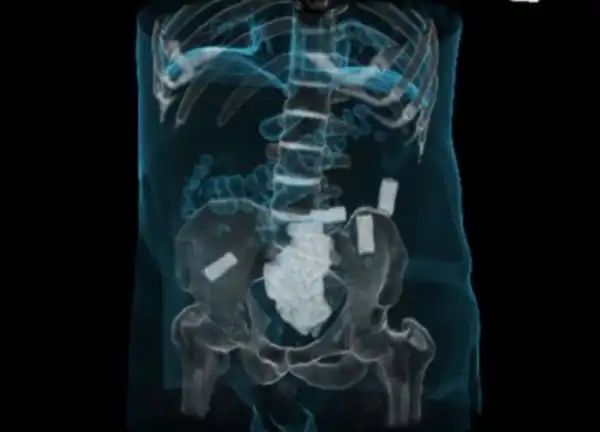

Девять пакетов кокаина

Эти цветные пакетики наркотиков находятся в толстой кишке

Наркотики в толстой кишке